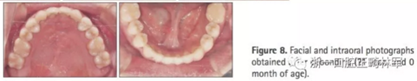

頭側結果顯示上頜輕度后縮(SNA 79.1°; A to N,-5.0mm;A到VRP水平距離為57.5mm),下頜輕度前突(SNB,80.2°,Pog-N-7.2mm;POG到VRP水平距離,57.4mm),低角ANB(-1.1°),正常下頜平面角(FMA,29.5°),正常下頜角(119.8°),上頜切牙斜度正常(U2 to SN,106.7°)和下頜切牙的舌傾角(IMPA,85.0°)。正常的覆合和覆蓋(覆合,1.7mm,覆蓋,1.9mm)(圖8和9,表3)。

2年后隨訪提示治療結果得到保持(圖10,11,表1-3),不同階段的頭側重疊結果見圖12。